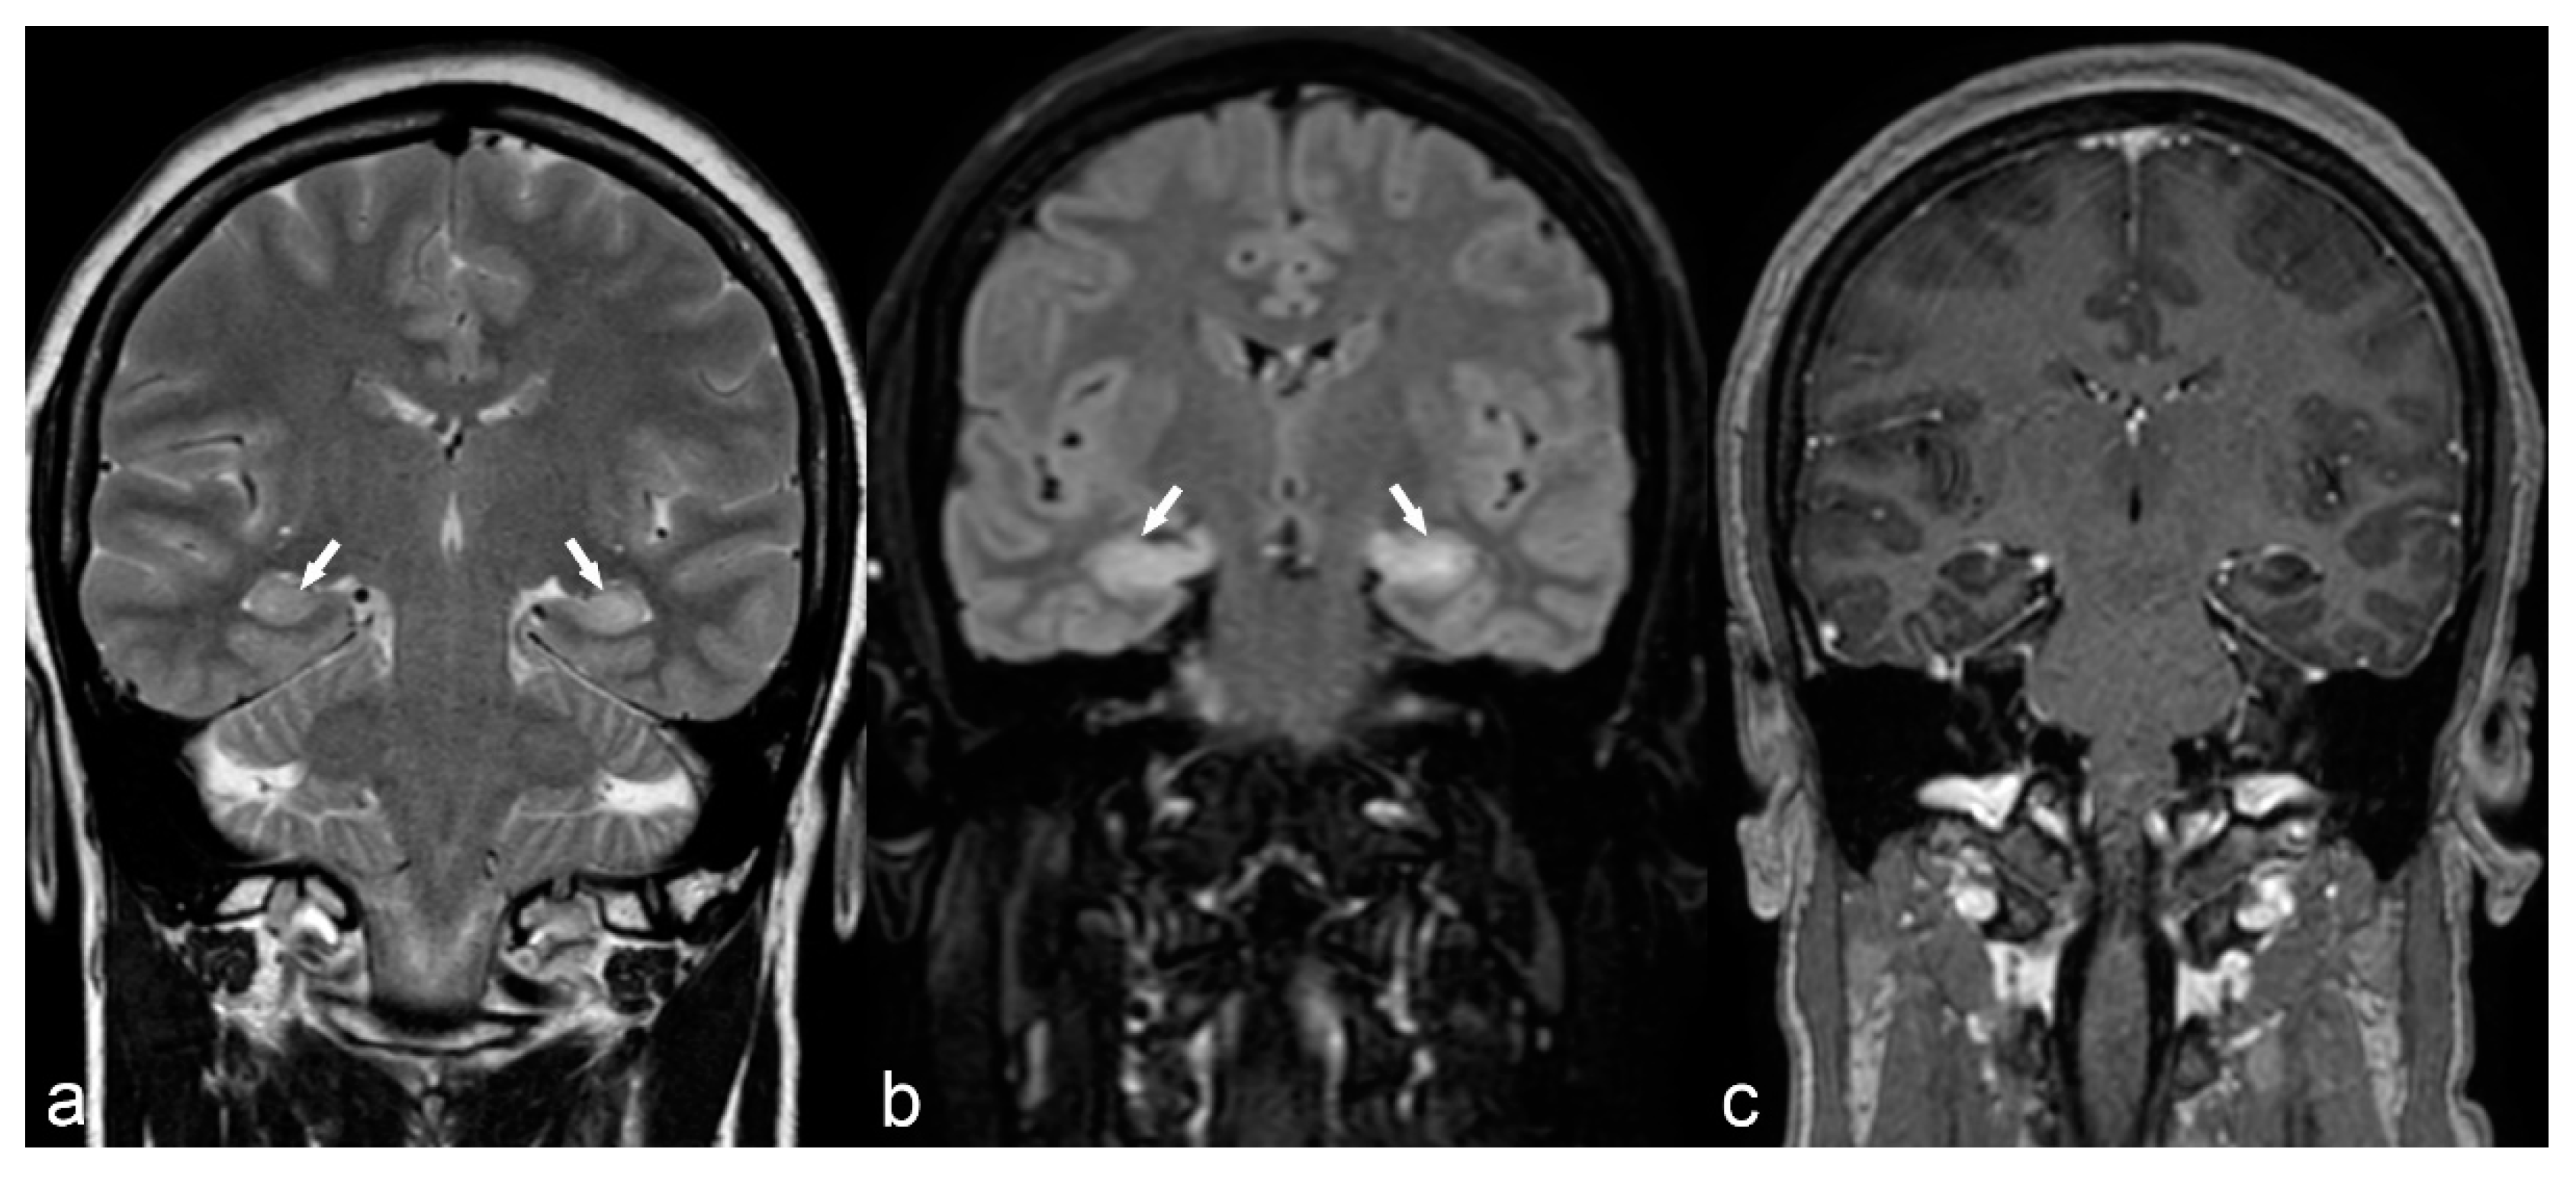

Figure 5.

10-year-old girl with cortical dysplasia. There is thickening of the cortex on the left mesial fronto-parietal region (arrows in (a) to (f)) associated to funnel-shaped hyperintensity of the surrounding white matter (arrows in (b,e)). Note blurring between the white and gray matter interface (f).